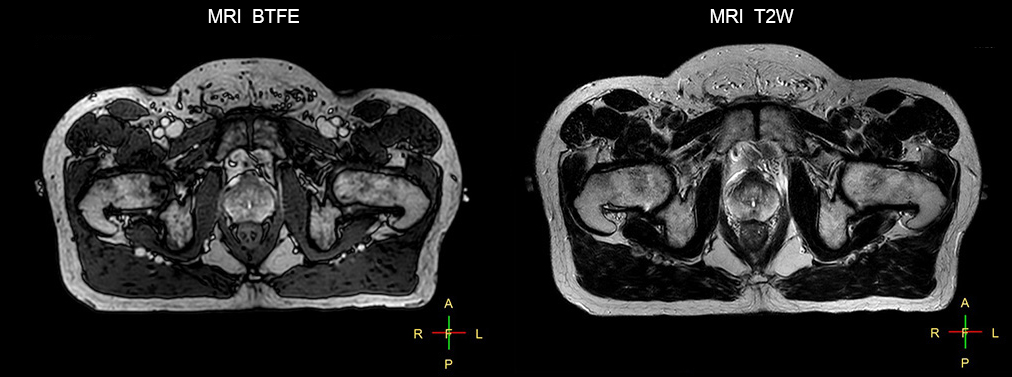

Beaumont Health System (Royal Oak, Michigan, USA) is one of the largest health systems in the USA, with eight hospitals and 153 outpatient sites, a medical school and a research institute. The Radiation Oncology (RO) department houses a dedicated Ingenia MR-RT solution that is routinely used for clinical and research MR-RT activities. “The main reason to integrate MR imaging in RT planning is the superb soft tissue contrast that allows detailed delineation of tumors and healthy organs, which is crucial for RT planning,” says Craig W. Stevens MD, PhD. “MR also provides information on functional and biological activities in tumors, background tissue and normal organs, which may also be used in RT planning,” says physicist Di Yan, DSc, FAAPM.” “We currently use MR-RT mainly in the abdomen and pelvis region: prostate, colorectal, pancreatic, cervical, and liver. Also in the brain, we are starting to use it,” says Dr. Yan.

“The biggest problem for CT-based planning, especially in prostate, is you can’t see the cancer very well,” says Dr. Stevens. “On CT it can be quite challenging to see the edge of the prostate especially at the apex. When the edge of the prostate can’t be delineated well on CT, radiation oncologists will increase their margins a little bit so they don’t miss it, but that can also increase toxicity.” “Using MR, the prostate is well delineated. We quickly see the edges of cancerous tumors like in prostate cancer, and as normal structures can be defined, we can optimize the treatment plan to protect these organs and their normal function. This can potentially improve the outcome. And it improves workflow as well. We can contour more quickly, confident that the tumor is going to be in the field.” “The Ingenia 3.0T MR scanner provides high resolution allowing us to make scans fast for the patients. It also gives the potential to include methods like MR spectroscopy and diffusion weighted Imaging, which we’re in the process of doing right now,” Dr. Stevens adds.

“There are some general challenges in RT imaging – even with CT – such as imaging geometry and positioning accuracy. Positioning is extremely important in RT, because we need reproducibility between imaging and treatment position. We also need accurate geometry so we can be sure our treatment plan is properly delivered during the treatment,” says Dr Yan. “The Ingenia MR-RT configuration includes an external laser positioning system for patient alignment and a flat tabletop for imaging the patient in treatment position. Ingenia MR-RT also came with a special QA package for regular monitoring of precision. Our Ingenia 3.0T scanner achieves good geometric accuracy – within a millimeter for most patients – and the phantom measurement is even better,” he adds. “Ingenia’s wide 70 cm bore is valuable to easily accommodate immobilization devices needed in RT,” says Dr. Stevens. “With a small bore MR scanner you can’t get the RT immobilization devices into the scanner properly; the large bore makes it easy to image patients in their immobilization device.”